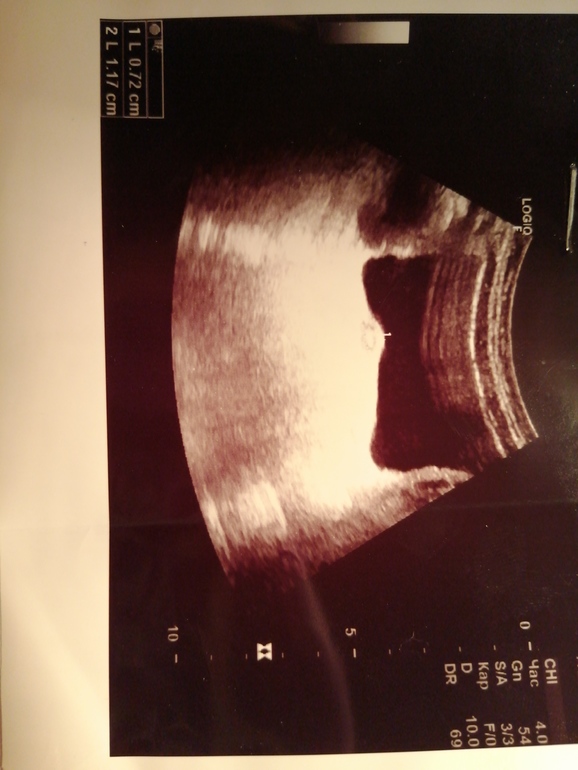

Уретероцеле?

Здравствуйте, девочка 7 лет жалобы на частое мочеиспускания, моча норма, отправили на узи. Диагноз уретероцеле по вопросом. Хирург сказал что ничего не видит и это не уретероцеле а матка, после совещания с гинекологом подтвердил ещё раз это. Но посоветовал сделать узи повторно позже. Мочеиспускания частые уже 2 месяца. Посмотрите пожалуйста снимок, стоит ли нам беспокоиться?

Здравствуйте. Для подтверждения диагноза нужны другие исследования. УЗИ не объективный критерий